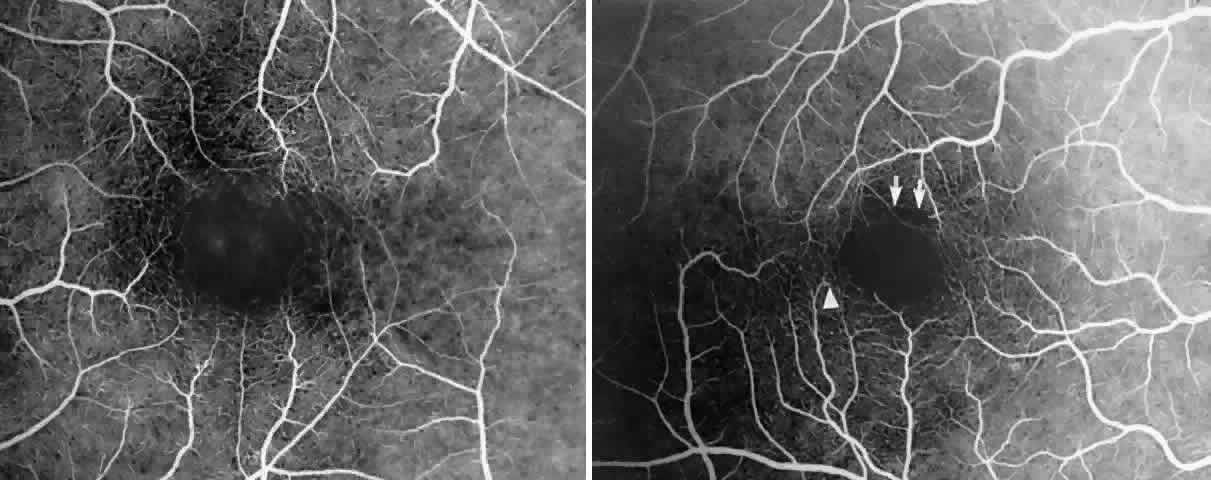

STAGE III: PRERETINAL NEOVASCULARIZATION (PROLIFERATIVE SICKLE RETINOPATHY). “Sea fan”-shaped neovascularization typically develops on the venular side of an arteriolar-venular anastomosis, mimicking the normal development of retinal capillaries (Fig. 24).125 A lowered oxygen tension and angiogenic factors released on the venular side may be the stimulus for neovascular growth.125,126 In most instances, the direction of growth is toward the ora serrata, from the perfused retina toward the nonperfused retina. Presumably, this represents an abortive attempt to revascularize the nonperfused retina, initiated by vasoproliferative factors.

The characteristic neovascular lesions of PSR are called sea fans because they resemble the marine invertebrate Gorgonia flabellum.70 They tend to occur more commonly in the temporal periphery, but they have been reported to occur in the temporal macula in the presence of extensive nonperfusion.130,133 Initially they grow on the surface of the retina, but they often become elevated into the vitreous and adhere to a partially detached posterior hyaloid.114 It may be difficult to visualize small sea fans ophthalmoscopically; however, fluorescein angiography clearly demonstrates leakage of dye into the vitreous (Fig. 25). The feeding arteriole is usually more tortuous than the draining venule (Fig. 26). Early on, the neovascular lesion is fed by a single arteriole and drained by a single venule, but with time, additional arterioles and venules become arborized within the lesion (Fig. 27).129 Growth of the sea fan often occurs circumferentially, rather than radiallyÜmh- 1Ý, toward the ora serrata. Progressive circumferential growth may lead to neovascular lesions extending around the entire periphery. As it matures, a white fibroglial mantle often covers the neovascular tissue (Color Plate 2B).

|

|